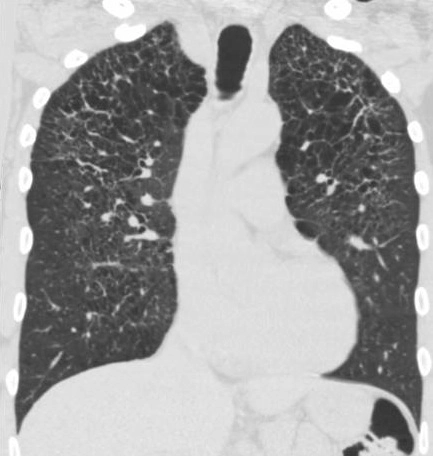

• Bệnh Erdheim-Chester (Erdheim-Chester Disease - ECD)